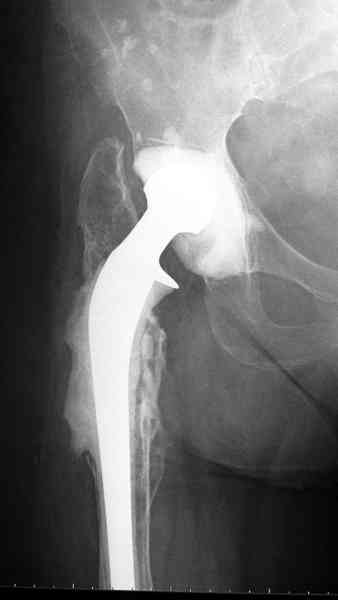

Наглухо ушитая рана с дренажом зажила первично, после чего с больной потерял контакт, и только недавно, через 8 лет я осмотрел её. Она без проблем нагружает на конечность и передвигается с помощью трости. От окончательной операции по реконструкции отказывается, довольная результатом.

Имеются литературные данные, когда спейсер держали не более 6 месяцев, но этот случай бьет все рекорды, может быть для наших людей, обременных финансовыми трудностями, нужна другая шкала оценки сроков нахождения спейсеров.

и последние снимки.